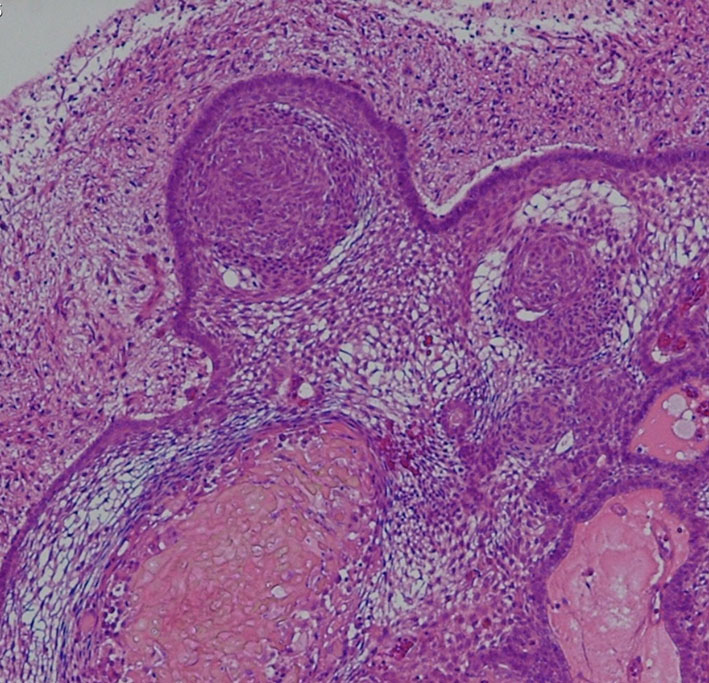

- 病理は,fibrovascular coreを中心として,ケラチンを含まない分化度の高い”非角化型”扁平上皮の単純な増殖です

成人の第3脳室内部に局在する頭蓋咽頭腫です。経脳梁法で両側のモンロー孔から全摘出しました。下垂体組織は残っています。これは乳頭状頭蓋咽頭腫と呼ばれるもので,成人にしか発生しません,のう胞がなく石灰化もないのが大きな特徴です。境界が明瞭で柔らかく摘出が簡単なタイプとして知られています。この患者さんも術後に下垂体機能不全も視床下部障害も生じませんでした。

Monomorphous mass of well-differenciated squamous epithelium lacking surface maturation and wet keratin.